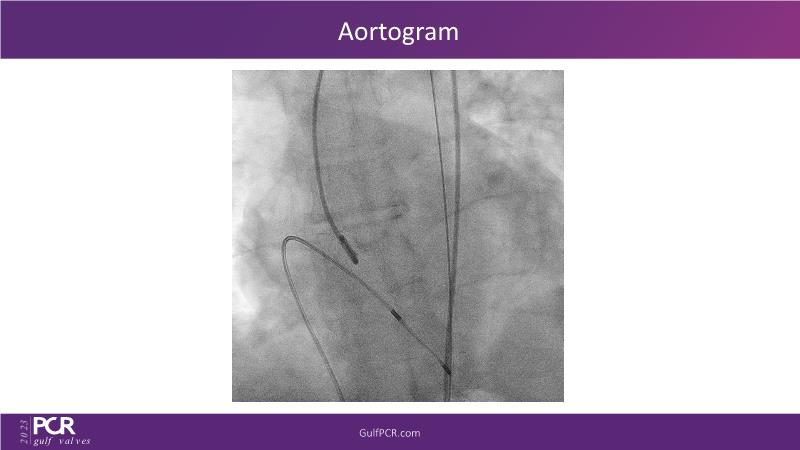

Essentials of lifetime management of TAVR patients using novel Myval THV

Join this GulfPCR-GIM 2023 session to explore the Myval next-generation THV technology, uncovering its unique features, procedural advantages, and clinical benefits, from extensive patient data. Learn also about the CorAlign technique that ensures precise commissural and coronary alignment while preserving coronary access, and gain insights into the precise sizing, positioning, and deployment techniques for the Myval THV.

- To understand the CorAlign technique which enables predictable and precise commissural and coronary alignment thus preserving coronary access